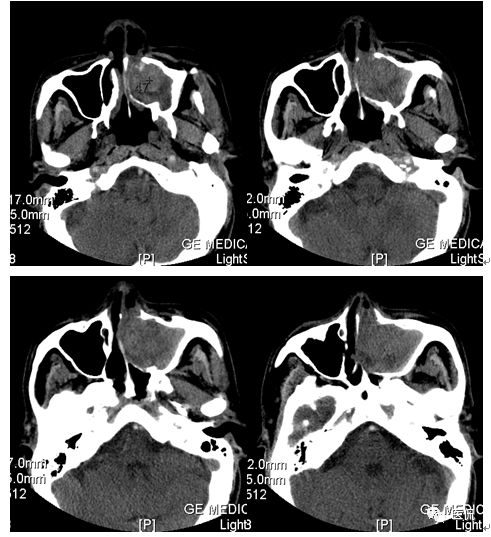

增强静脉期

CT平扫及增强示:左侧上颌窦及鼻腔可见软组织密度影,呈膨胀性生长,周围骨质压迫性吸收破坏,累及左眶,病灶密度不均匀,周边区可见点状钙化,增动脉期轻度强化,局部见小灶性稍高密度区,静脉期病灶内见不均匀明显强化,CT值最高达117HU,延迟期强化范围有所增大。

影像学表现呈软组织密度,多不均匀,表现为高低混杂密度,病变窦腔内息肉、血肿、坏死、感染共存,是病灶密度不均匀的主要原因,息肉反复出血、血管机化亦为其成因之一。病灶内钙化,可为团块状或小片状,可能为病变组织坏死后钙质沉着所致。由于病变组织内有大量炎性细胞浸润和丰富的毛细血管,增强后常有强化。有文献报道病灶增强中心区强化不明显,外周呈轻度强化,推测病灶内虽然血管丰富,但中心区容易出现血流动力学障碍,血管内常有血栓形成,中心区易发生出血坏死,另外,可能与增强扫描延迟时间选择不当有关。

本例病灶较大,周围骨质可见吸收破坏,并累及眼眶,病灶内少量钙化,增强扫描具有一定特征性,表现为动脉期轻度强化,局部见小灶性稍高密度区,静脉期病灶局部呈明显强化,CT值最高达117HU,延迟期强化范围有所增大,呈延迟渐进性强化的特点,推测为病灶内出血所致。